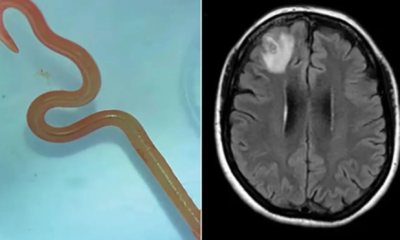

El gusano identificado como Ophidascaris robertsi suele vivir en el esófago y el estómago de las pitones diamantinas. Creen que la mujer tocó o ingirió una...